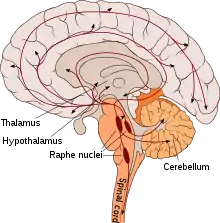

A serotonin pathway identifies aggregate projections from neurons which synthesize and communicate the monoamine neurotransmitter serotonin. These pathways are relevant to different psychiatric and neurological disorders.[1][2][3]

Given the wide area that the many serotonergic neurons innervate, these pathways are implicated in many functions, as listed above. The caudal serotonergic nuclei heavily innervate the spinal cord, medulla and cerebellum. In general, manipulation of the caudal nuclei(e.g. pharmacological, lesion, receptor knockout) that results in decreased activity decreases movement, while manipulations to increase activity cause an increase in motor activity. Serotonin is also implicated in sensory processing, as sensory stimulation causes an increase in extracellular serotonin in the neocortex. Serotonin pathways are thought to modulate eating, both the amount as well as the motor processes associated with eating. The serotonergic projections into the hypothalamus are thought to be particularly relevant, and an increase in serotonergic signaling is thought to generally decrease food consumption (evidenced by fenfluramine, however, receptor subtypes might make this more nuanced). Serotonin pathways projecting into the limbic forebrain are also involved in emotional processing, with decreased serotonergic activity resulting in decreased cognition and an emotional bias towards negative stimuli.[5] The function of serotonin in mood is more nuanced, with some evidence pointing towards increased levels leading to depression, fatigue and sickness behavior; and other evidence arguing the opposite.[6]